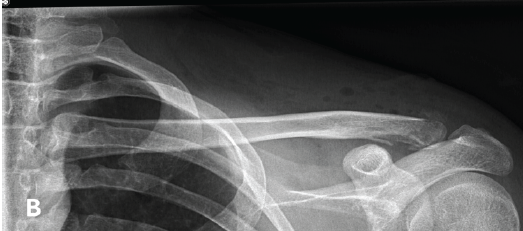

Spontaneous Remodeling of Posterior Sternoclavicular Joint Dislocations in Skeletally Immature Patients: A Case Report

Abdalla O. Abdalla , Eoin Fahey , Rebecca Lyons , David Morrissey